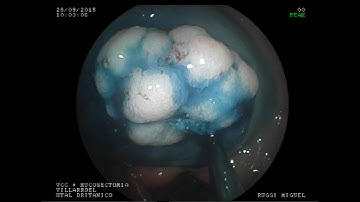

UNDERWATER EMR OF LARGE LST-NG IN ASCENDING COLON